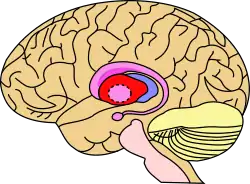

The putamen is a structure in the forebrain. Along with the caudate nucleus it forms the dorsal striatum. The caudate and putamen contain the same types of neurons and circuits – many neuroanatomists consider the dorsal striatum to be a single structure, divided into two parts by a large fiber tract, the internal capsule, passing through the middle. The putamen, together with the globus pallidus, makes up the lentiform nucleus. The putamen is the outermost portion of the basal ganglia. These are a group of nuclei in the brain that are interconnected with the cerebral cortex, thalamus, and brainstem. Basal ganglia include the dorsal striatum, substantia nigra, nucleus accumbens, and the subthalamic nucleus.

In mammals, the basal ganglia are associated with motor control, cognition, emotions, learning, and domain-general functions important for executive functioning as well as support for domain-specific languages. The basal ganglia are located bilaterally, and have rostral and caudal divisions. The putamen is located in the rostral division as part of the striatum. The basal ganglia receive input from the cerebral cortex, via the striatum.